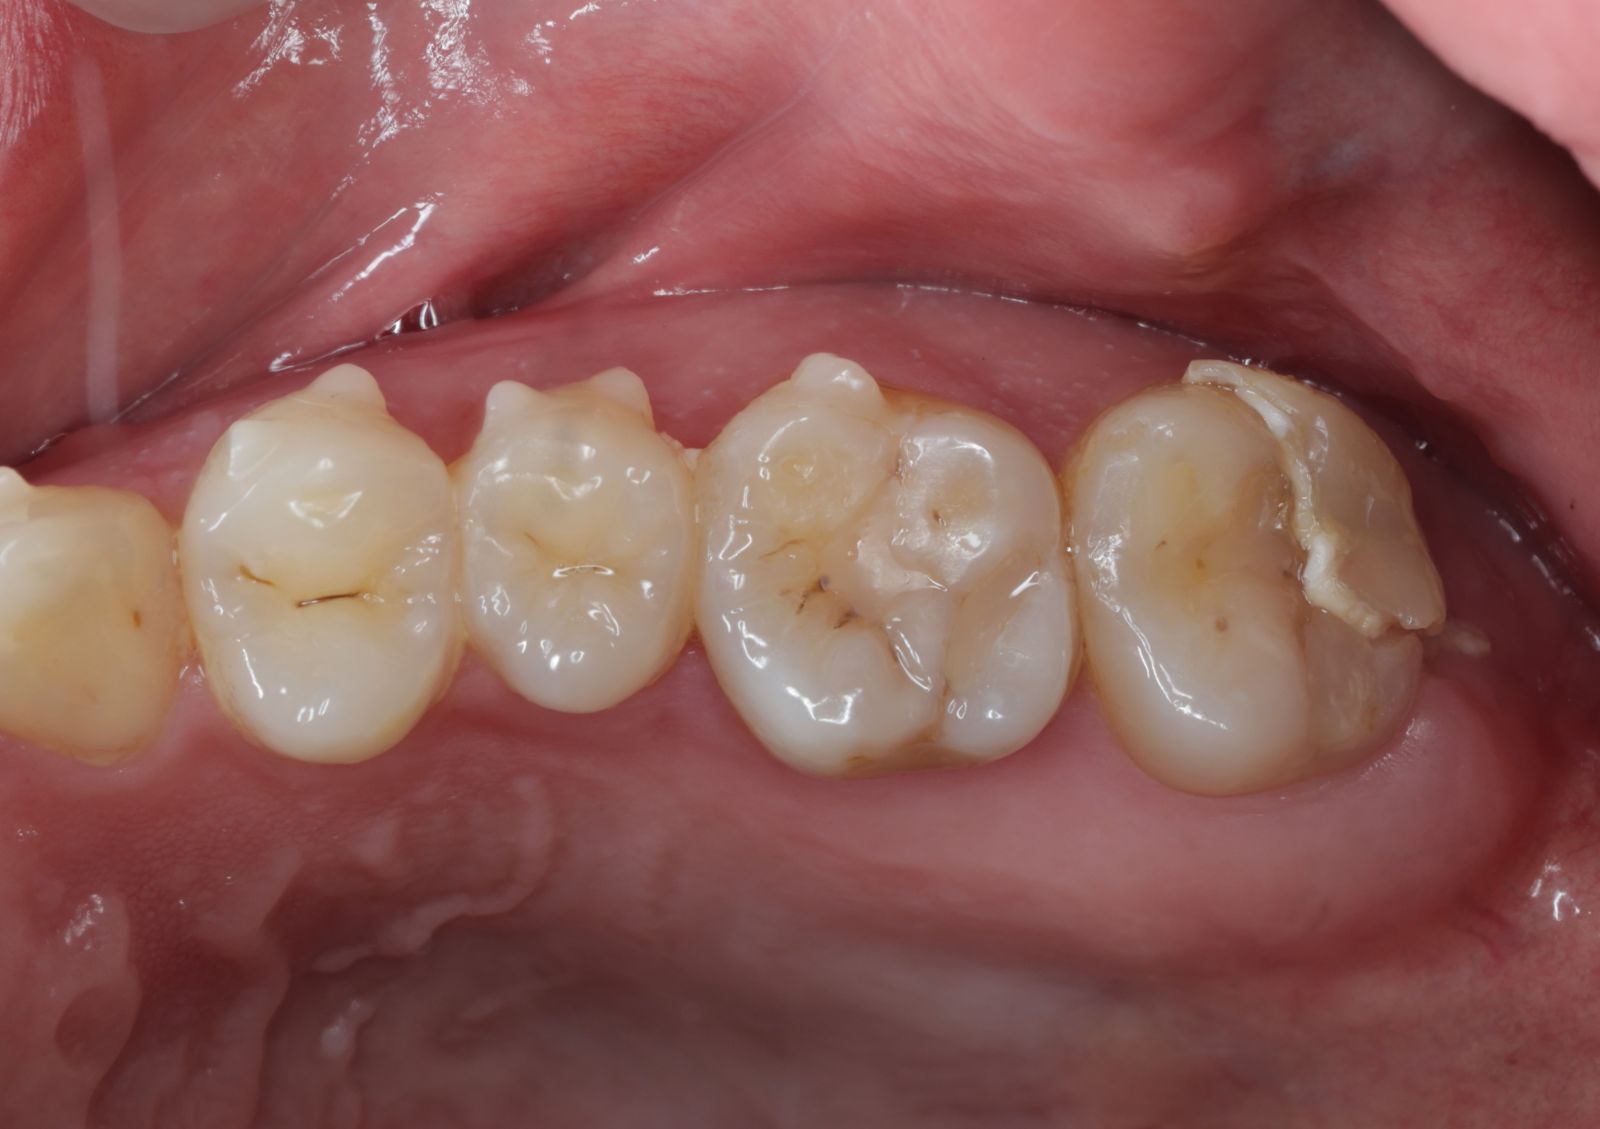

【 案 例 一 】

- 以前大範圍的樹脂補牙,久了造成二次蛀牙,不只是材料不密合,原本的牙齒還可能斷裂。把蛀牙挖乾淨後,隔絕感染源再印模,待陶瓷齒雕送回後再以特殊黏膠黏著完成!經過全陶瓷齒雕修復後,跟原先相比之下,牙齒恢復外型以外還能增強牙齒強度。